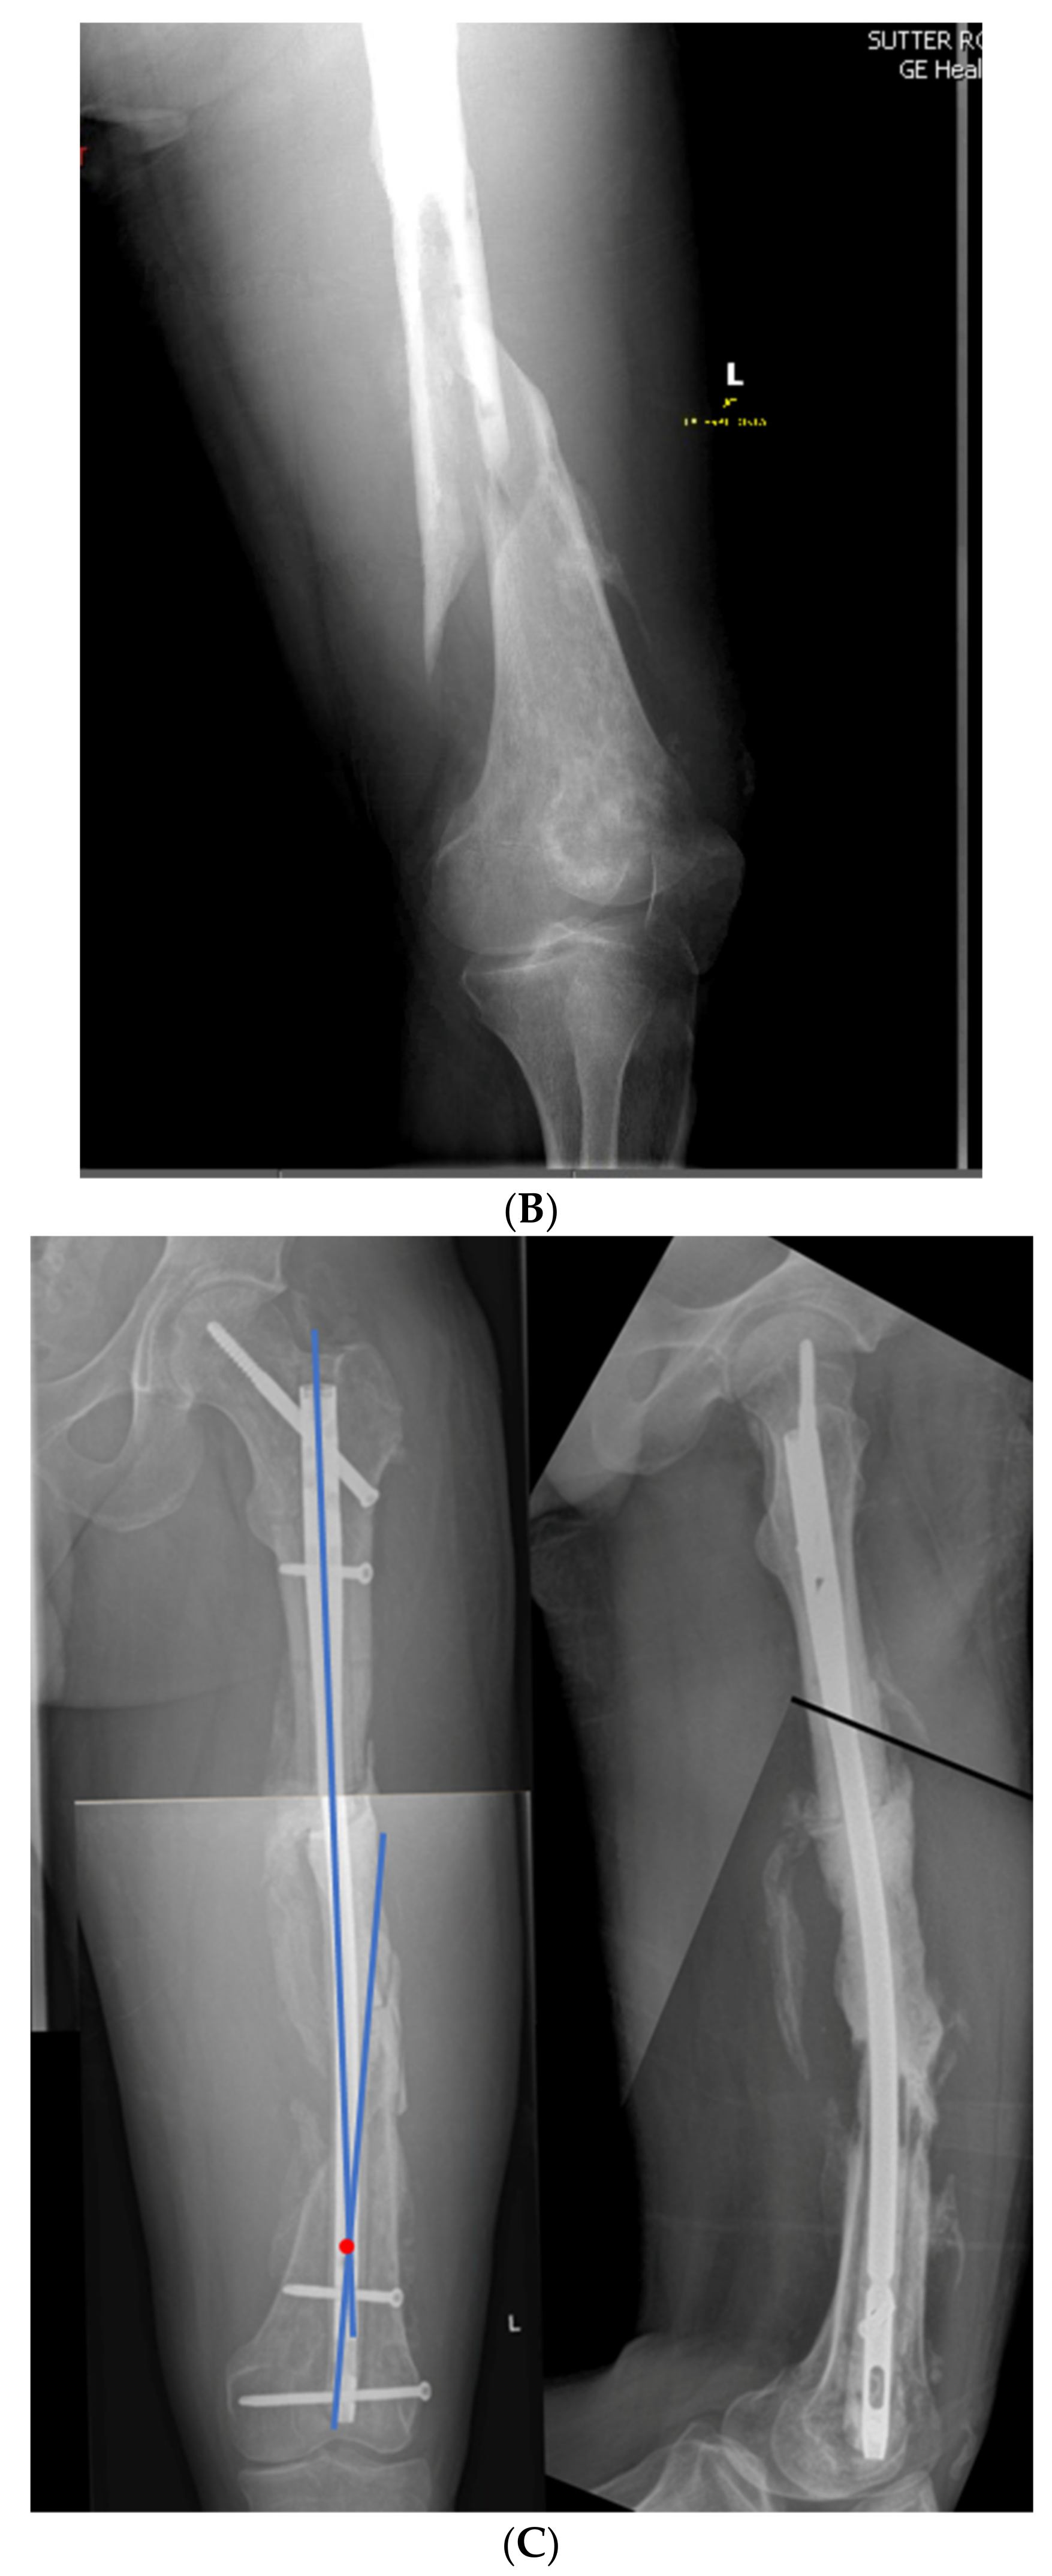

3.1. Case 1-Multifocal Correction with Intramedullary Nail: Femur

The patient is a middle-aged female with no comorbidities other than obesity who presented 26 years after an open diaphyseal femur fracture with more than 10 surgeries for attempted union and eradication of infection. The patient presented with complaints of pain at the mid-femur and knee, a chronically draining sinus of the lateral thigh, and concern for a 2-cm-short left leg. No rotational deformity is found. The limb clinically appears normal in the coronal plane. The patient has a 15-degree knee contracture. X-rays reveal a malunion of the left femur with bone sequestrum and retained hardware (Figure 6A). A metabolic workup, including the vitamin D level, is normal. The CT scan characterizes the pathological bone, allowing for precise localization of the sequestrum (Figure 6B). A deformity analysis reveals a primarily sagittal plane deformity with limb shortening. The traditional CORA analysis demonstrates translation with angulation, as demonstrated by a CORA located outside of the deformity. With the expected multiple stages, a double-level focal dome was chosen over clamshell, allowing stable weight-bearing while not requiring an extended femoral osteotomy to heal through pathological bone. The other consideration for this patient was radical en bloc resection of the diseased bone, with either bone transport or secondary reconstruction with a compressed allograft intercalary segment. This concept was reserved as the option if the current plan failed.

(A) Middle-aged female with 26 years of an infected draining sinus of the left femur with malunion and shortening. The intersection of the two blue lines represents the CORA of the proximal and distal diaphyseal segments (C1). A CORA outside of the deformity reveals translation in addition to angulation. The intersection of the green line with each blue line represents an alternative where the central deformed segment is also incorporated into the analysis, revealing two CORA center points for double-level osteotomy (Ca and Cb). (B) The patient was found to have retained hardware and a bone sequestrum. Sequestrectomy with antibiotic local delivery via a coated intramedullary nail with concomitant systemic antibiotics would promote infection eradication. (C) The patient underwent double-level focal dome osteotomy at the time of initial debridement. The patient had two sequential debridements over 10 days. Stabilization using an interlocking antibiotic coated nail was placed during the final debridement. (D) Five months postoperative, where the distal osteotomy was autogenous-grafted from the patient’s contralateral femur due to the persistent osteotomy gap. Chronic suppression oral antibiotics were recommended; patient voluntarily stopped antibiotics at 24 months. (E) Three-year final follow-up with normal serological markers and no sign of recurrence. Osteotomies healed. Soft tissue healed.

The patient underwent double osteotomy using focal dome osteotomy at Ca and Cb (Figure 6C), with retained hardware removal and resection of the infected sequestrum and surrounding diseased bone. A direct lateral approach to the thigh was used, and the diseased soft tissue track was excised and analyzed by pathology. A temporary nail was inserted and replaced with an antibiotic-coated interlocking nail ten days later with a planned second debridement. The nail was compressed using the internal compression instrumentation associated with the nail. A gap in the distal osteotomy persisted despite attempted removal of the nail and re-reaming with enlarging flexible reamers. This gap was accepted with intent to revisit if bone healing did not progress. The surgical soft tissue approach healed without incident. At five months postoperative, with nonunion of the distal osteotomy at the gap, the patient underwent autograft using contralateral femur reamer–irrigator–aspirator harvesting (Figure 6D). Cultures at the grafting procedure were negative.

The patient progressed to pain-free union at both osteotomies with no recurrence of her infection over three years after osteotomy (Figure 6E).